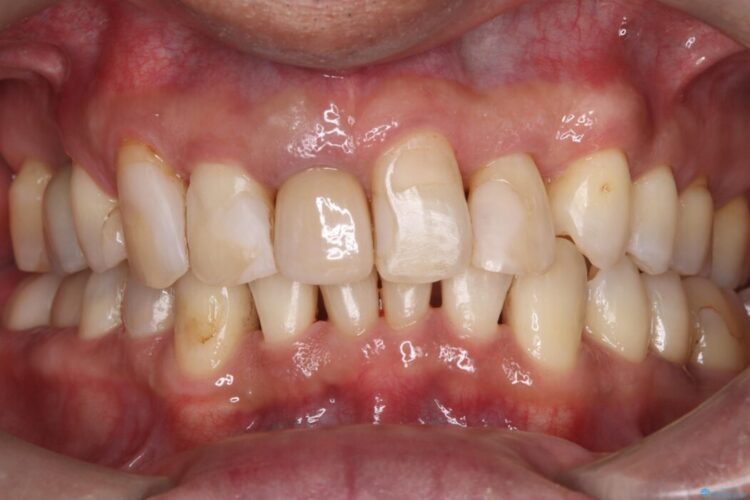

長期的な安定性を重視したセラミック治療

歯と歯の間に虫歯があった患者様です。

治療期間(治療回数):1ヶ月(2~5回) | 概算治療費:13.2万円(税込)(仮歯:10,000円+オールセラミッククラウン 3年保証110,000円)